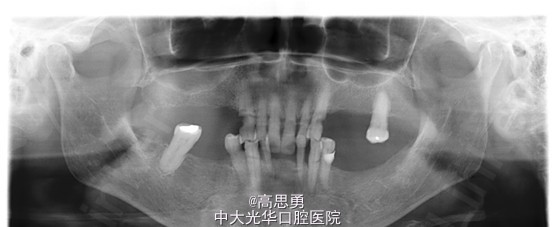

检查(包括专科检查及辅助检查): 1、全身状况良好,无全身系统性疾病,自主行动能力正常。精神心理状态无异常。 2、颌面部左右对称,面部比例协调,面部正面形态尖圆形。颞下颌关节运动无异常,开口型无异常,颞下颌关节无弹性,无压痛。 3、口内黏膜未见瘢痕,舌运动无异常。唇颊系带附着无异常,唾液分泌无异常。 4、牙龈正常,无肿胀无瘘管。 5、口内检查: #32近中移位约1mm,无明显倾斜 #44远中移位约2mm,向缺隙侧倾斜,伸长约1mm 其余缺牙间隙正常 全口牙龈退缩至根颈1/3,牙龈无肿胀无瘘管 上颌缺牙区牙槽嵴无明显吸收、下颌缺牙区牙槽嵴吸收呈低平刃状 口腔卫生状况欠佳、全口牙石多 11 12 13 14 15 16 17 21 22 23 24 25 26 27 视 存 存 存 缺 缺 缺 缺 存 存 存 缺 缺 缺 存 探 - - + - - - - - - - - - - - 叩 - - + - - - - - - - - - - - 松 - - I° - - - - - - - - - - - 楔 O O O - - - - O O O - - - - 31 32 33 34 35 36 37 41 42 43 44 45 46 47 视 缺 存 存 存 缺 缺 缺 缺 存 存 存 缺 缺 存 探 - - - - - - - - - - - - - - 叩 - - - - - - - - - - - - - - 松 - - - - - - - - - - - - - - 楔 - - O - - - - - O O O - - - 根尖X片示:13 根尖部阴影,牙颈部硬组织部分缺损 转诊牙体牙髓科后复诊 修复科第二次就诊口内检查: 11、12、13、21、22、23、33、42、43、44牙颈部见黄色充填物 13 探(-)、叩(-)、松(-),HE面见白色暂封物 口腔卫生状况尚可、牙石少,其余牙叩(-)、松(-) 根尖X片示:13 根尖部阴影,根充可 其余同前

诊断: 1、牙列缺损(上颌肯氏II类I分类,下颌肯氏II类II分类) 2、#13慢性根尖周炎 3、#11、#12、#13、#21、#22、#23、#33、#42、#43、#44楔状缺损 4、慢性牙周炎 治疗计划 1、#13转牙体牙髓科做RCT 2、转牙体牙髓科对#11、#12、#13、#21、#22、#23、#33、#42、#43、#44楔状缺损 充填治疗 3、转牙周科进行牙周洁治 4、择期RPD修复 备选修复方案: 1、#13RCT后截冠后,上下颌覆盖义齿修复; 2、#13RCT后冠修复,上下颌可摘局部义齿修复; 3、#13RCT后树脂充填,上下颌可摘局部义齿修复; 4、#13拔除后,上下颌可摘局部义齿修复。 患者意愿:患者希望尽量保持#13的天然形态,要求费用尽量低,但能恢复正常咀嚼功能。 最终治疗方案:根据患者的年龄、身体状况、治疗周期、经济状况,患者最终选择方案5,即#13RCT后树脂充填,上颌结合卡环式可摘局部义齿修复;下颌可摘铸造支架式局部义齿修复。 治疗过程: 1、临床检查和#13树脂充填 对患者进行全面的口腔检查,用Z350树脂充填#13,调HE,抛光。 2、研究模型 调拌藻酸盐印模材料于2号成品托盘上取上下颌研究模,灌注石膏模型,研究分析、制定治疗计划,并制作个别托盘。 3、基牙预备 对#13近中、#23远中、#27近中、#34近中、#47近中常规制备支托凹,抛光。 4、工作模型 调拌藻酸盐印模材料于个别托盘上。做一定的边缘整塑,取上下颌研究模,灌注石膏模型。 5、试戴支架 检查支架的就位、固位可,无翘动,调HE,抛光,用蜡堤取颌位关系,上颌架,排牙,比色C4。 6、试排牙 检查义齿的就位、固位可,无翘动,观察人工牙的咬合状况,尖窝接触良好,正中颌位能重复,患者无诉不适,面容自然,外观满意。送加工厂充胶制作最终修复体。 7、试戴 检查义齿的就位、固位可,无翘动,咬合关系正确,利用咬合纸检查,上下颌尖窝接触均匀全面,抛光,患者表示满意,嘱注意事项,定期复诊。